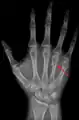

![]() Fourth metacarpal of the left hand (shown in red). Palmar view. | |

The fourth metacarpal bone (metacarpal bone of the ring finger) is shorter and smaller than the third.

The base is small and quadrilateral; its superior surface presents two facets, a large one medially for articulation with the hamate, and a small one laterally for the capitate.

On the radial side are two oval facets, for articulation with the third metacarpal; and on the ulnar side a single concave facet, for the fifth metacarpal.